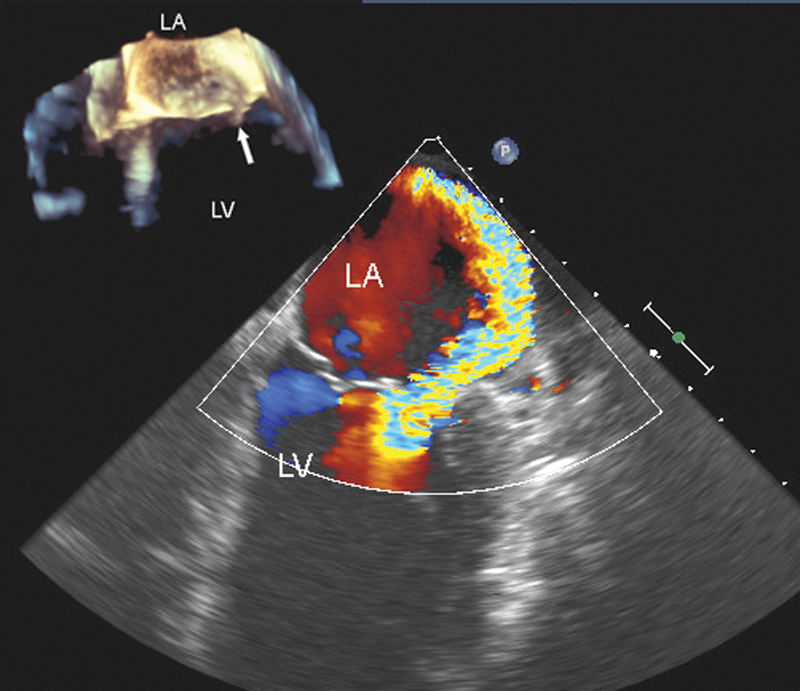

فحوصات تشخيصية لبعض امراض القلب والشرايين التاجية